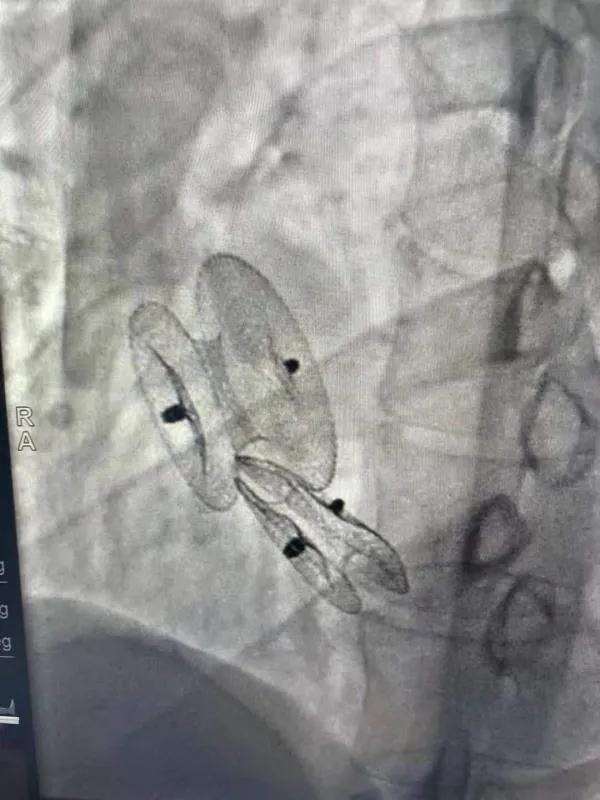

先天性心臟病房間隔缺損呈多孔型怎么辦?患者并非只能選擇開胸手術(shù)。近日,西安國際醫(yī)學(xué)中心醫(yī)院心臟病醫(yī)院成功開展一例雙孔房間隔缺損雙傘介入封堵術(shù)。

房間隔缺損是先天性心臟病的一種,介入手術(shù)相較于傳統(tǒng)的外科手術(shù)損傷小,風(fēng)險(xiǎn)相對(duì)較低,術(shù)后恢復(fù)快。一般的房間隔缺損多呈單孔,封堵難度較小,而雙孔房間隔的封堵難度大大增加,至今僅有國內(nèi)頂尖的封堵專家成功完成了數(shù)例而已。

患者是位27歲的年輕女性,經(jīng)常感到心慌,心臟超聲發(fā)現(xiàn)房間隔缺損,并且房間隔缺損呈雙孔型,大的約14mm,小的約9mm,兩個(gè)缺損間相隔較遠(yuǎn),介入封堵難度非常大。

在詳細(xì)了解患者病情,仔細(xì)閱讀患者影像資料后,曾廣偉主任已經(jīng)有了清晰的手術(shù)策略。在精心的準(zhǔn)備和團(tuán)隊(duì)的配合下,曾主任順利的利用兩個(gè)封堵器對(duì)房缺進(jìn)行了封堵。